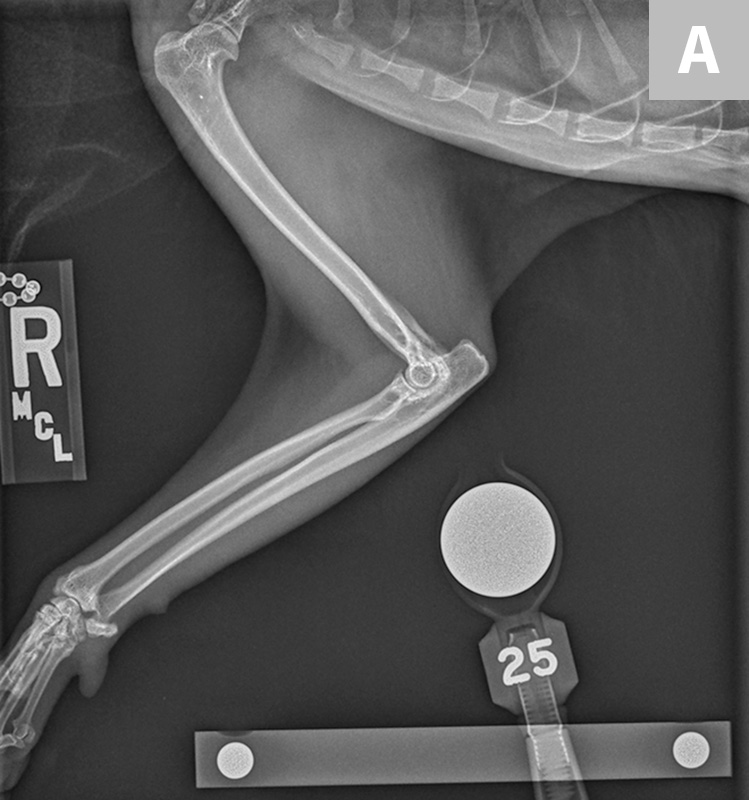

From www.cliniciansbrief.com

Pain Management in an Arthritic Senior Cat Clinician's Brief Cat Arthritis Age Cat arthritis is a common condition that causes painful joints and makes moving uncomfortable. There is no cure for cat arthritis,. If your cat has had an accident at some point in their. Technically, arthritis can affect a cat at any age, but it is most commonly seen in cats ages 6 years or older. These are the most common. Cat Arthritis Age.